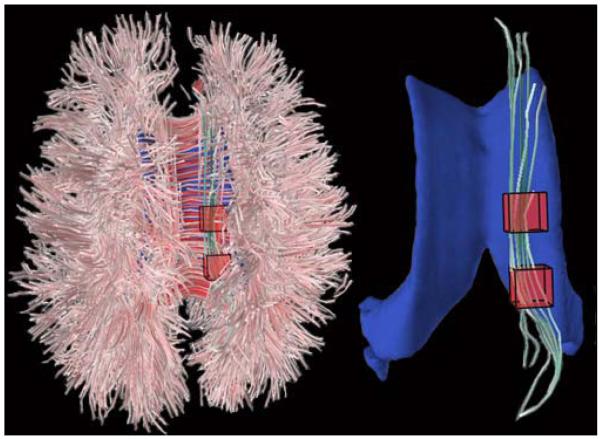

Figure 3 shows an example of cingulum bundle selection in a patient with VCI.

Figure 3.

Cingulum bundles segmented from a 76-year-old patient with VCI. Left image shows placement of voxels-of-interest in axial view (top of image is anterior). Right image shows segmented cingulum bundle. Lateral ventricles are depicted in blue for reference purposes.